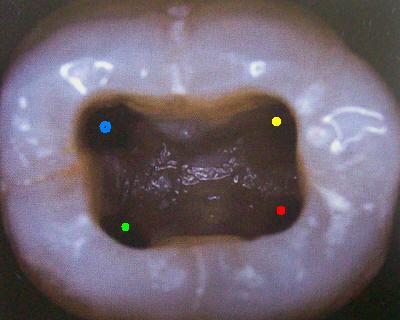

Cuarto conducto en molares inferiores (Color amarillo)

Cuando tiene tres conductos el mas amplio es el distal con una sección oval y su curvatura es suave o recta. Si presenta cuatro conductos la raíz distal contendrá dos de ellos y son de diámetro más pequeño y en caso de presentar dos conductos, ambos son amplios.